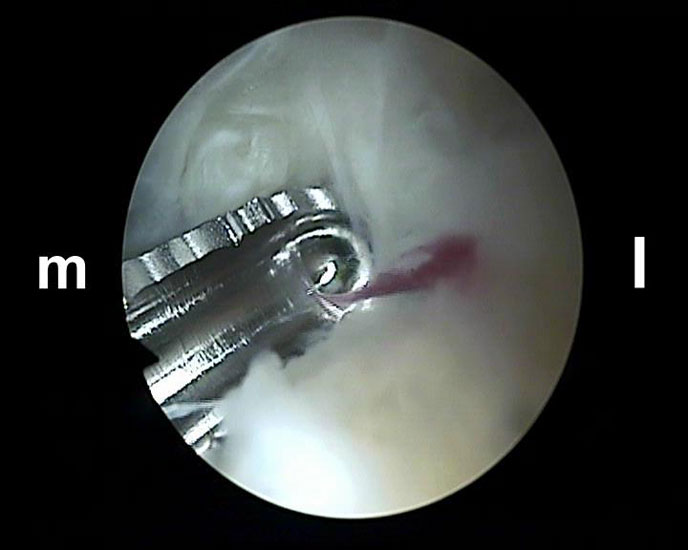

Abbildung Nr. 5-7

Über das laterale Portal wird ein 4,0 mm Arthroskop senkrecht nach ventral eingebracht mit der Zielrichtung auf den 1. Interdigitalraum. Zur Orientierung kann mit dem stumpfen Wechselstab zunächst der Kontakt zum Knochen getastet werden. Es lassen sich so auch die dorsale Tibiakante, der Proc. posterior des Talus und die craniale Begrenzung des Kalkaneus identifizieren. Ist das Arthroskop über das laterale Portal eingeführt, wird die Blickrichtung nach lateral ausgerichtet. Von medial wird ein Weichteilshaver eingeführt, dessen Arbeitsöffnung nach ebenfalls lateral weist. Die Instrumente werden in der Weise trianguliert, dass die Shaverspitze unmittelbar vor dem Arthroskop identifiziert werden kann (rechte Seite, m=medial, l=lateral).

Abbildung Nr. 8-10

Es wird zunächst ein Weichteildebridement durchgeführt, bis die Flexor hallucis longus-Sehne identifiziert werden kann. Während des Debridements sollte auf die korrekte Ausrichtung der Instrumentenöffnung nach lateral geachtet werden. Im Verlauf empfiehlt sich der Wechsel auf eine bipolare Ablationselektrode, die eine gezielte Freilegung der Strukturen unter gleichzeitiger Blutstillung ermöglicht, ohne dabei unkontrolliert Gewebe anzusaugen (rechte Seite, m=medial, l=lateral). Das Os trigonum bzw. die Osteophyten sowie die FHL-Sehne müssen vollständig dargestellt werden (*=Os trigonum, FHL=Flexor hallucis longus-Sehne).